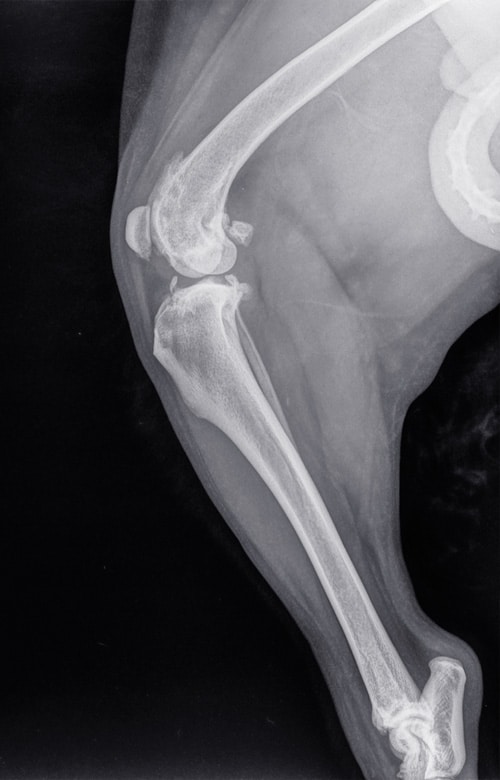

A Tibial Plateau Leveling Osteotomy is performed to treat cranial cruciate ligament (CCL) tears, one of the most common orthopedic injuries in dogs. Rather than repairing the ligament directly, this surgery changes the angle of the tibial plateau (the top of the shinbone) to stabilize the knee and prevent abnormal forward motion. Our doctors will examine your pet and discuss whether TPLO surgery is the most appropriate option. Tibial Plateau Leveling Osteotomy (TPLO)